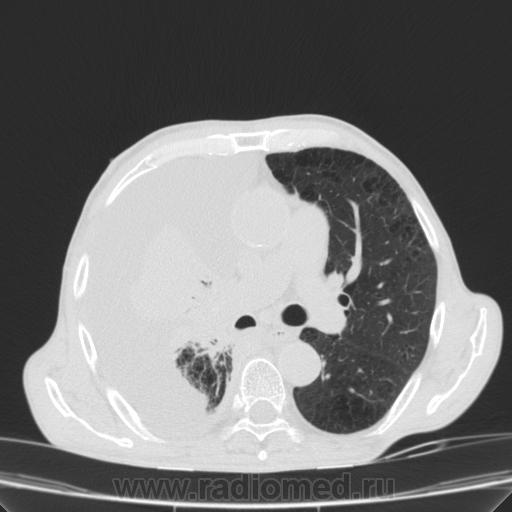

Пожилой мужчина, лечился по н/д правостороннней пневмонии в терап/отделении. Жалобы на одышку, кашель. По результатам Р-контроля после лечения направлен на КТ легких с диагнозом: плеврит справа, распад? В корне правого легкого вижу объёмное образование, с распадом. Смущают размеры плеврита,очень много жидкости, почти до 3 ребра. Анализы крови спокойные- L4,0-6,6, СОЭ 12-16мм. Неужто ТБС, отсев бы был при таком огромном поражении. В посеве мокроты-100% высев клебсиэллы пневмоние. Мокрота на общий анализ в работе-собирает с трудом, изза отсутствия мокроты. Плевральную пункцию еще не проводили. Н азначила бронхоскопию и плеврал пункцию. Как думаете, уважаемые коллеги, это онкопроцесс или тбс распад?

Самое интересное забыла показать- может это 100% навеет на мысль об опухолевом процессе, остеолитическая деструкция позвонка?

Не смотря дайкомы, только по рентгенограмме, предположил бы центральный рак правого легкого. Потому что большой гидроторакс, без смещения средостения в здоровую сторону, как правило, соответствует раковому ателектазу.

Коллеги, распада там нет, это вас медиастинальное окно подвело. В грудине тоже все в порядке. Да и компрессия позвонка "старая".

Небольшое количество увеличенных лимфоузлов, и те - не сказать, чтоб были очень крупными. От эмпиемы до онкологии... Умеренное количество жидкости в перикарде, толщиной слоя до 13-14 мм. При подобной картине не вижу смысла гадать по сжатому лёгкому, пишу так: массивный выпот справа, около 2500 мл, диафрагма оттеснена жидкостью каудально, печень (!!!) смещена каудально и вправо. Легкое справа значительно компрессировано жидкостью, оценка проходимости бронхов и состояния легочной паренхимы (кроме имеющейся эмфиземы) практически невозможна. Необходима пункция плевральной полости справа (цитология, ВК, посев на микрофлору и проч), КТ-контроль после эвакуации жидкости.